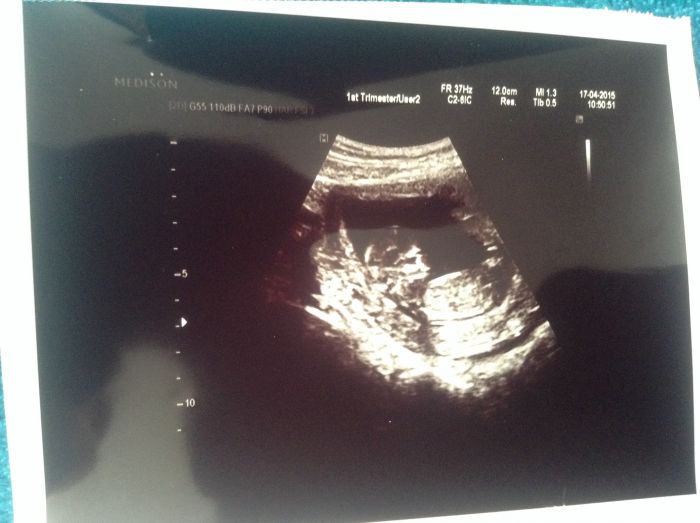

Leni, myslím na tebe a držím palečky. Ze zkušenosti vím, že statistika je svinstvo a nikdy nefunguje tak, jak má :D. Takže pevně věřím, že v tuto chvíli pracuje pro tebe :). Jinak u nás vše ok, prcek na utz pěkně hopsal. Dost mě překvapilo, že jsme za foto nic neplatili. I když je pravda, že kvalita je taká vachrlatá :D, ale kdo by si stěžoval ... Dneska ráno byl můj žaludek milosrdný a nechal mě spát, ale za to střeva zavelela v půl 6. Jsem měla pocit, že se mi tam snad váže gordický uzel. Asi na vteřinu mě napadlo, že to je prcek, páč to přestalo hned, jak jsem se otočila na bok. Ale říkám si, že je dost brzy, že mám asi dost bujnou fantazii :D.